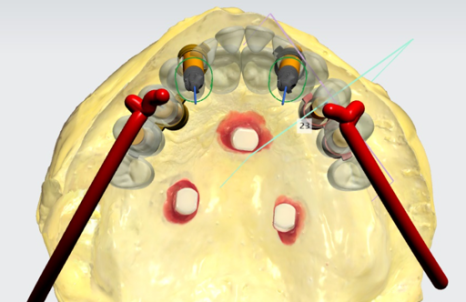

『임플란트 수술 계획도 철저히』

뼈가 이미 많이 퇴축이 되어있기에,

뼈가 많이 얇은 상태입니다.

표기 해놓은 위치만큼,

상악동거상술 이라는 술식을 접목시켜서

하방에 뼈 이식을 진행해야 됩니다.

하악에 있는 턱 뼈 또한,

뾰족하게 솟아오른 것을 볼 수 있죠.

앞서 설명드린 것 처럼

뼈 이식을 계획했습니다.

그러면서 전체 악궁을 놓고 봤을 때

밸런스가 잘 맞는지도 같이 살펴보게 됩니다.

신경 쓸게.. 정말 많죠?